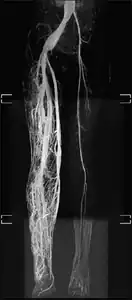

Angiogram: an angiogram can also be ordered to get a detailed look at the blood vessels in the affected or overgrown limb. In this test a physician injects a dye into the blood vessels that will help see how the blood vessels are malformed.[23]

MRI-dilated turtuous blood vessels -

Angiogram